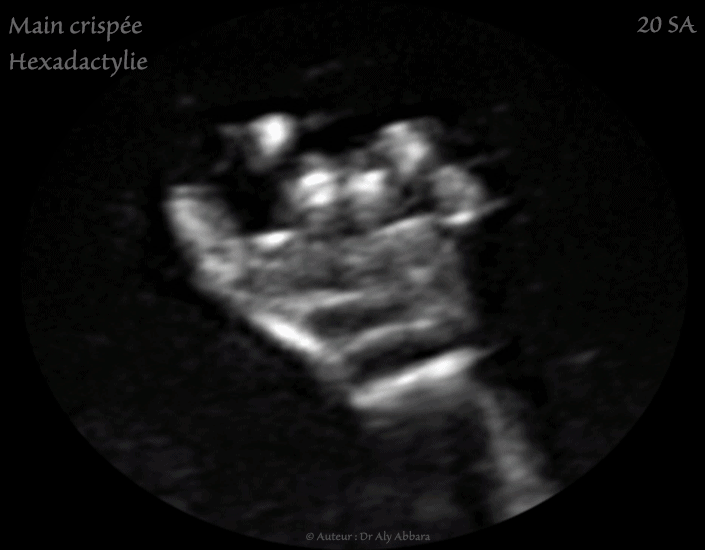

Images échographiques en 2D et en 3D montrant l'aspect ultra-sonre d'une main crispée avec chevauchement des doigts des mains : l'index recouvre le majeur et l'auriculaire recouvre l'annulaire.

Ce Signe est retrouvé dans 50 % des cas de trisomie 18.

L'hexadactylie est la deuxième malformation de la main identifiable sur ces images échographiques.

Par ailleurs, d'autres malformations ont été découvertes : omphalocèle, estomac non vu, large communication interventriculaire (CIV), micro-rétrognathisme, profil plat, agénésie du corps calleux, agénésie du vermis, placenta kystique, artère ombilicale unique, kyste du cordon ombilical et enfin, un retard sévère de la croissance in-utero (RCIU).